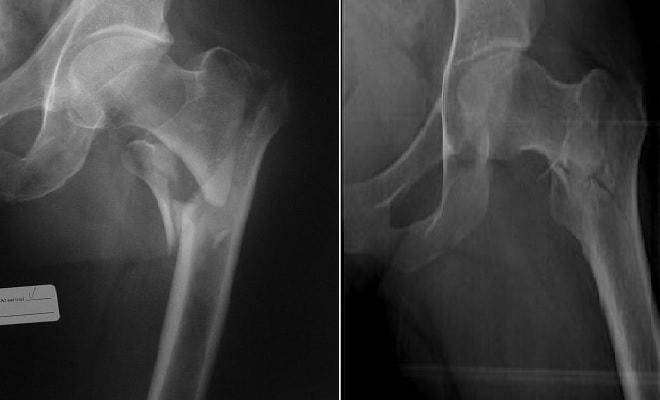

Для проведения диагностики межвертельных переломов необходимо обращаться в специализированное медицинское учреждение отделение травматологии лечебно-профилактического учреждения или травмпункт. Обследование проводится травматологом или хирургом. Врач опрашивает больного об обстоятельствах травмы, выясняет жалобы и анамнез болезни. Он обнаруживает отёчность бедра, ограничение подвижности в тазобедренном и коленном суставах на стороне поражения. Выявляет кровоподтёк в зоне перелома, определяет границы распространения отёка.

Назначают следующие дополнительные виды исследования:

- рентгенографию бедренной кости в двух проекциях;

- компьютерная томография области тазобедренного сустава;

- при подозрении на наличие гематомы назначают МРТ.